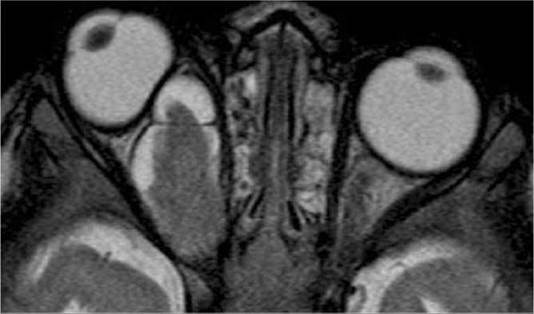

2. MRI of the brain and orbits only if indicated by a sign or symptom, including ophthalmic findings of optic nerve dysfunction, optic nerve pallor/swelling/shunt vessels, or proptosis.

(See Figures 13.13.1 and 13.13.2.)

FIGURE 13.13.2 Optic nerve glioma.